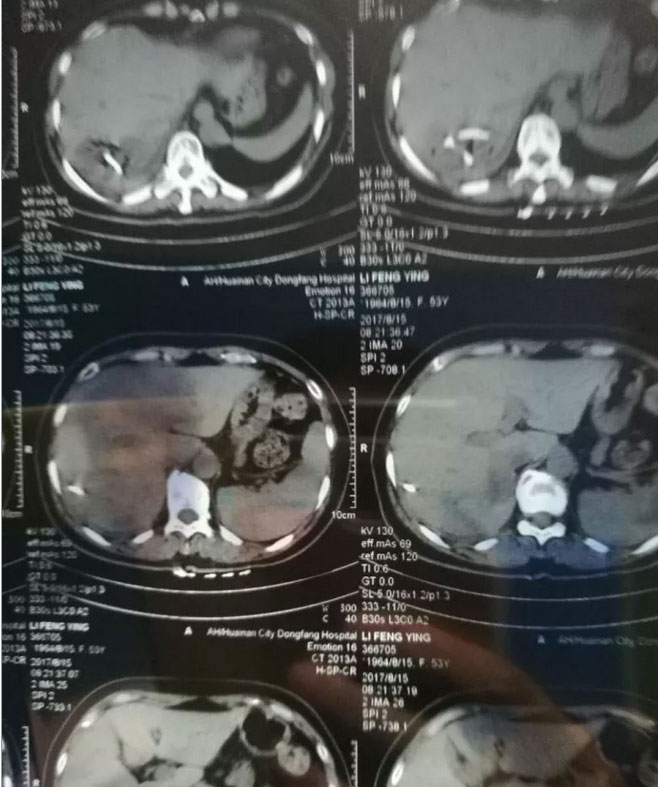

2017年5月,一位潘集的农村患者,高烧不退,在当地医院住院治疗症状没有缓解,后求诊于总院普外科。经CT检查后发现肝脏右后叶低密度灶,结合患者病史,考虑为肝脓肿。在王品主任的带领下,在B超定位引导下行肝脓肿穿刺置换引流术,术后辅以抗感染及营养支持治疗,患者病情快速康复。